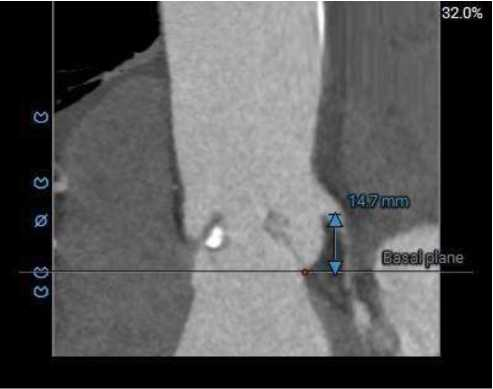

ANNULUS

LVOT

STJ

2mm SUPRA ANNULUS

4mm SUPRA ANNULUS

6mm SUPRA ANNULUS

8mm SUPRA ANNULUS

10mm SUPRA ANNULUS

12mm SUPRA ANNULUS